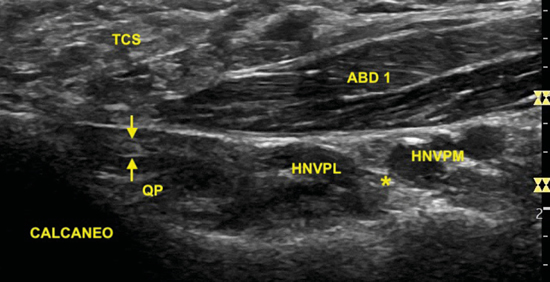

La imagen sonográfica se centrará en el espacio situado bajo la fascia profunda del músculo abductor del primer dedo, por donde discurrirán los haces neurovasculares plantar medial y plantar lateral, diferenciados y separados por el septo de Heimkes o interfascicular3. El nervio plantar medial se muestra con mayor sección que el nervio plantar lateral, y las venas laterales con mayor luz que las mediales (Figura 14).

Figura 14. El septo interfascicular (*) parte desde la fascia profunda del músculo abductor del primer dedo (ABD 1) hacia el tendón flexor largo del primer dedo (FLD) dividiendo la cámara superior de la cámara inferior, donde respectivamente se encuentran el haz neurovascular plantar medial (M: nervio plantar medial; A/V: arteria y venas plantar medial) y el haz neurovascular plantar lateral (L: nervio plantar lateral, A/V: arteria y venas plantar lateral). En profundidad, el músculo cuadrado plantar (QP) y la superficie del calcáneo (CAL).

Situamos la sonda tomando como referencia la línea entre el centro del calcáneo y el vértice del maléolo tibial (Figura 15). La ecografía muestra cómo la rama de Baxter se encuentra en el espacio comprendido entre la fascia profunda del músculo abductor del primer dedo y el músculo cuadrado plantar, en la cara próxima al calcáneo5. Debido a su pequeño tamaño, entre uno y dos milímetros11, el examen ecográfico de este nervio monofascicular en el espacio entre el músculo abductor del primer dedo y el músculo cuadrado plantar es posible, aunque se hace complicado5,12 (Figura 16).

Figura 16. Ecografía de la rama de Baxter (flechas) bajo la fascia del músculo abductor del primer dedo (ABD 1) próximo a su inserción en el calcáneo y sobre el músculo cuadrado plantar (QP). Se sitúa posterior al haz neurovascular plantar lateral (HNVPL) que se encuentra separado del haz neurovascular plantar medial (HNVPM) mediante el septo de interfascicular o de Heimkes (*). TCS: tejido graso subcutáneo.